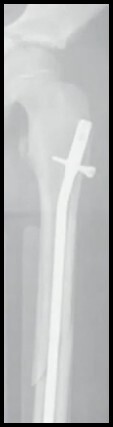

8

Q

FX Diafisária do Fêmur

TTO > 10 anos?

A

HASTE RÍGIDA

ou

Haste Flexível ( < 50 Kg)

Placa (Cominuição)